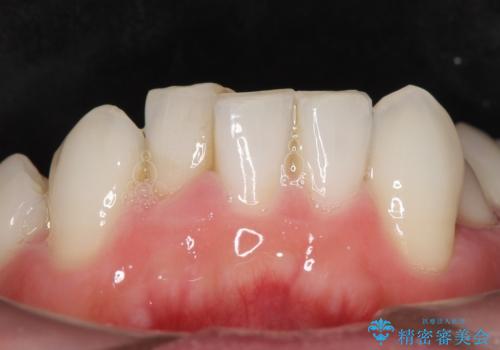

矯正治療とホワイトニングを提案しましたが希望されず、「接客関係の仕事で矯正治療は考えられない、短期間で治療を終わらせたい、ホワイトニングでは難しい位の人工的な白さにしたい」とのご要望により、治療前にワックスアップ模型を作製し何度もコンサルテーションを重ね、治療方針を決定しました。

歯頚ラインが変えられないことや天然歯を削るリスクをご理解頂いた上で、オールセラミッククラウンによる補綴治療を行いました。(見えない奥歯のみ天然歯のままとしました)

下の前歯1本だけ歯軸を変えるために神経をとり根管治療を行っております。

それ以外の歯は神経をとらずに済むよう、慎重かつ丁寧に歯の形態を整えました。

クラウンの色味に関して、自然な白さ(シェードA1~NW0.5)のクラウンを作製・試適したところ「もっと白くしたい」と希望され、当院で最も明度の高い色(シェードNW0)に修正しました。

被せ物の種類:オールセラミッククラウン スタンダード (シェード:NW0)